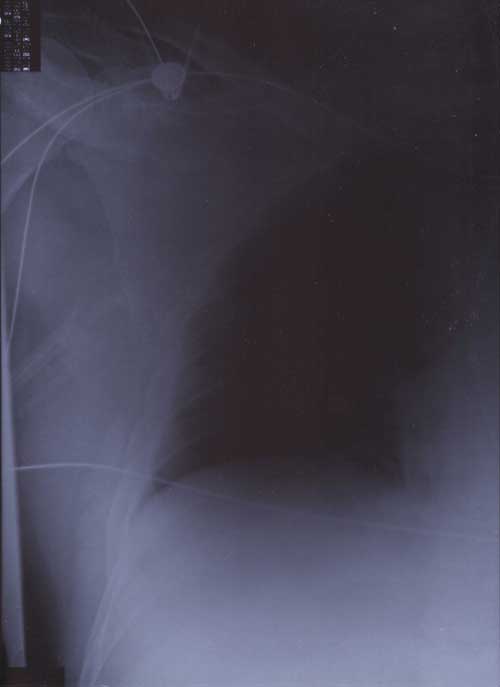

X Rays

22nd January 2000